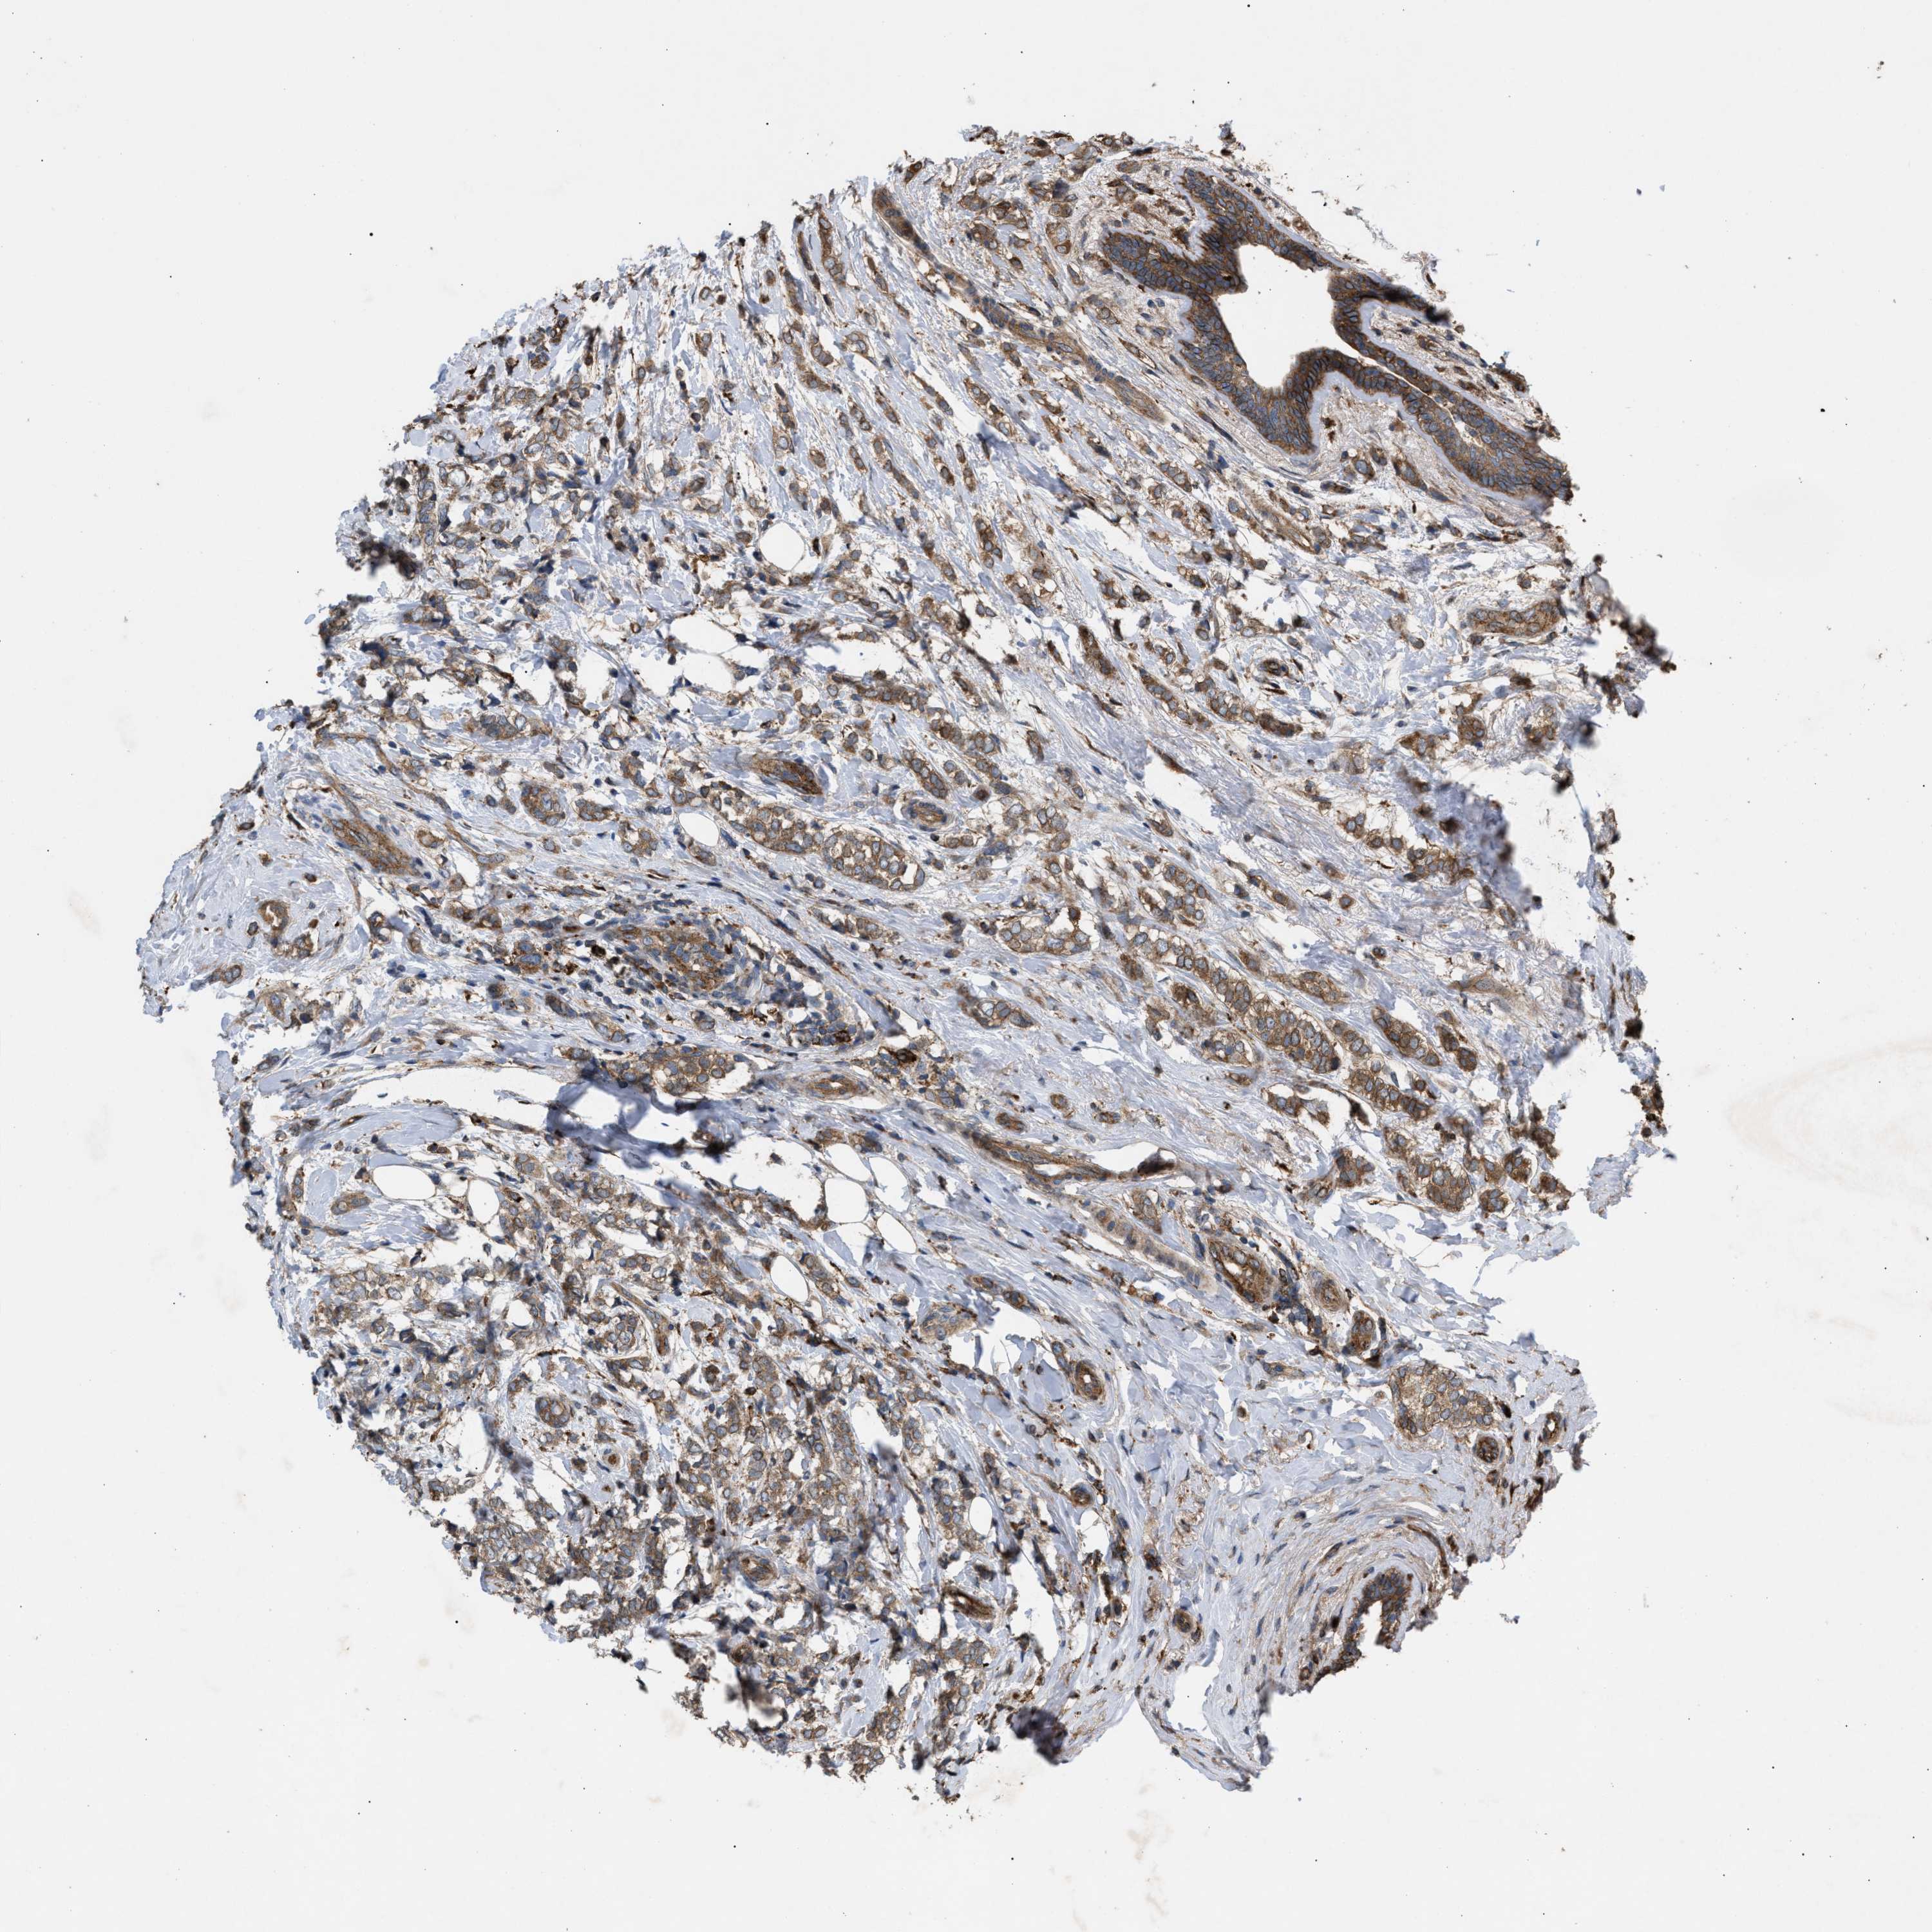

CANCER BREAST CANCER Show tissue menu

BRCA TCGA BRCA VALIDATION PROTEIN EXPRESSION

ANTIBODIES

AND

VALIDATION